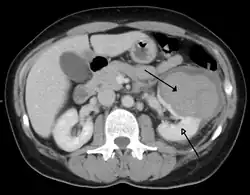

| Abdominal trauma resulting in a right kidney contusion (open arrow) and blood surrounding the kidney (closed arrow) as seen on CT | |

Kidneys

The kidneys may also be injured; they are somewhat but not completely protected by the ribs.[6] Kidney lacerations and contusions may also occur.[13] Kidney injury, a common finding in children with blunt abdominal trauma, may be associated with bloody urine.[13] Kidney lacerations may be associated with urinoma or leakage of urine into the abdomen.[4] A shattered kidney is one with multiple lacerations and an associated fragmentation of the kidney tissue.[4]